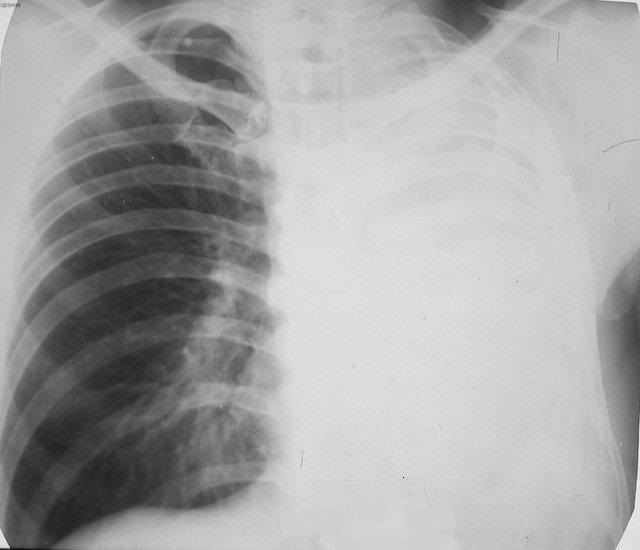

Как выглядит ателектаз на рентгене?

На прямой рентгенограмме хорошо виден ателектаз верхней доли правого легкого в виде однородного затемнения треугольной формы с четкими контурами.